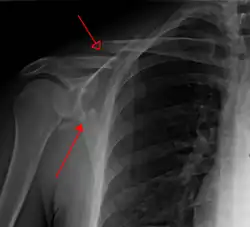

Most fractures of the scapula can be seen on a chest X-ray; however, they may be missed during examination of the film.[1] Serious associated injuries may distract from the scapular injury,[4] and diagnosis is often delayed.[3] Computed tomography may also be used.[1] Scapular fractures can be detected in the standard chest and shoulder radiographs that are given to patients who have had significant physical trauma, but much of the scapula is hidden by the ribs on standard chest X-rays.[4] Therefore, if scapular injury is suspected, more specific images of the scapular area can be taken.[4]